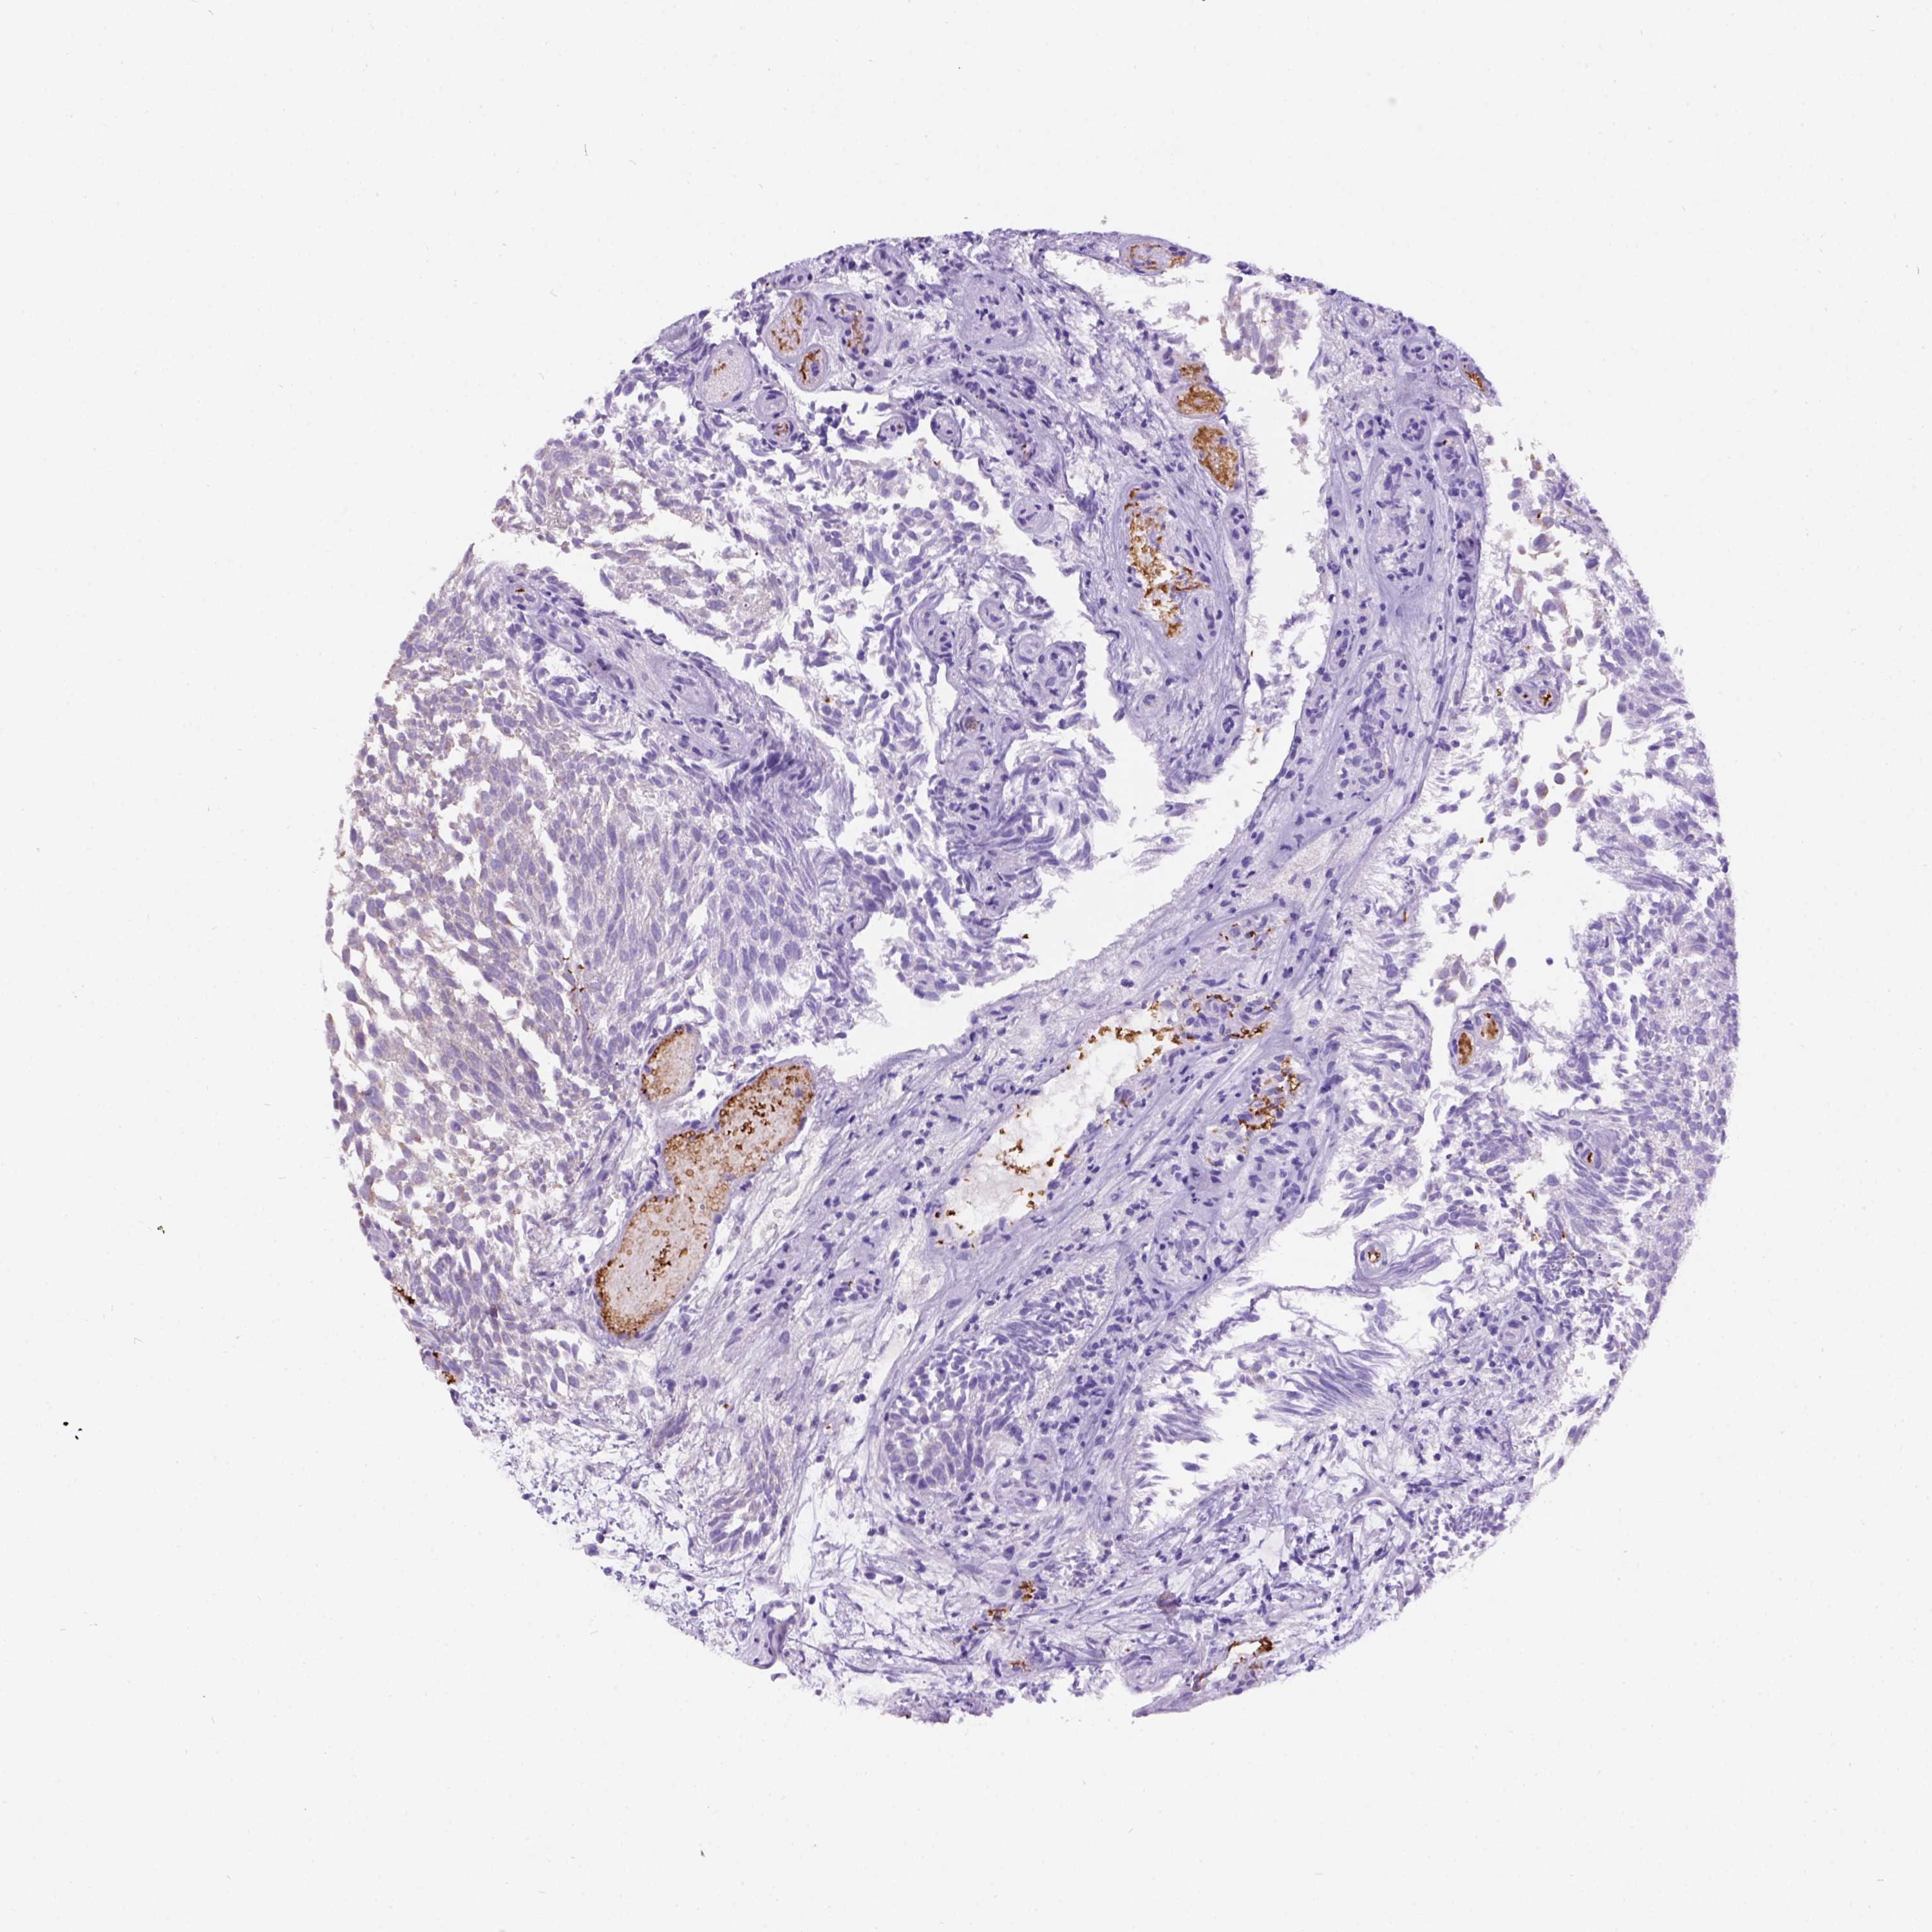

UROTHELIAL CANCER - Protein expressioni

A mouse-over function shows sample information and annotation data. Click on an image to view it in a full screen mode. Samples can be filtered based on level of antibody staining by selecting one or several of the following categories: high, medium, low and not detected. The assay and annotation is described here.

Antibody stainingi

Antibody staining in the annotated cell types in the current human tissue is reported as not detected, low, medium, or high, based on conventional immunohistochemistry profiling in selected tissues. This score is based on the combination of the staining intensity and fraction of stained cells.

Each image is clickable and will lead to virtual microscopy that enables deeper exploration of all samples and also displays staining intensity scores, fraction scores and subcellular localization as well as patient and tissue information for each sample.

Antibody HPA065409

Staining

High

Medium

Low

Not detected

Intensity

Strong

Moderate

Weak

Negative

Quantity

>75%

75%-25%

<25%

None

Location

Nuclear

Cytoplasmic/membranous

Cytoplasmic/membranous,nuclear

Urothelial carcinoma, High grade

Urothelial carcinoma, NOS

Urothelial carcinoma, Low grade